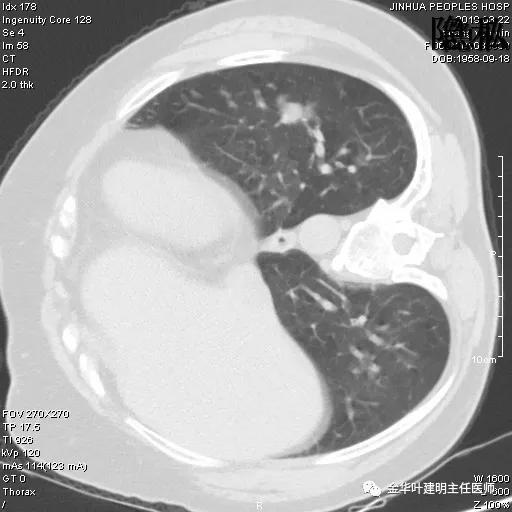

可见左肺下叶比较靠中央的部位也有一病灶,是混合磨玻璃影,偏实性,瘤肺边界清楚,是较为典型的肺癌表现。进一步的靶扫描图像如下:

靶扫描更清晰的显示细节,从影像上看,基本可以断定左下肺的是恶性肿瘤了,而且已经密度较高,长径也在3厘米以上,不能继续观察等待了!